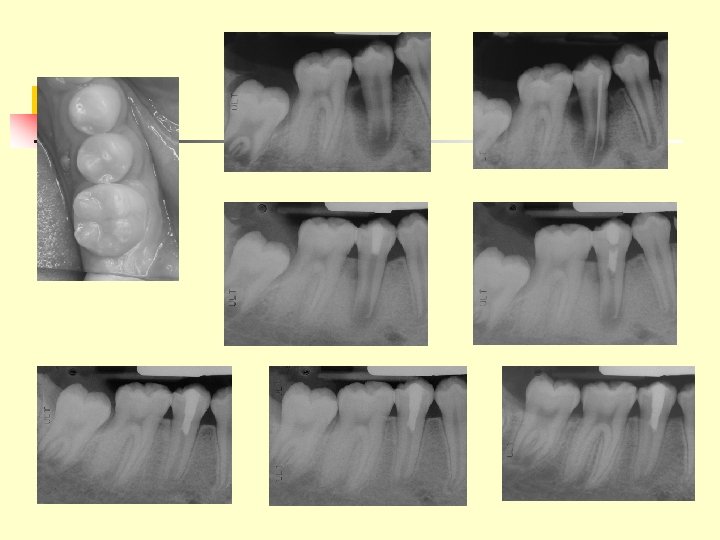

CH apexification 16/5/43 11/10/43 21/3/44 22/5/45 28/5/46